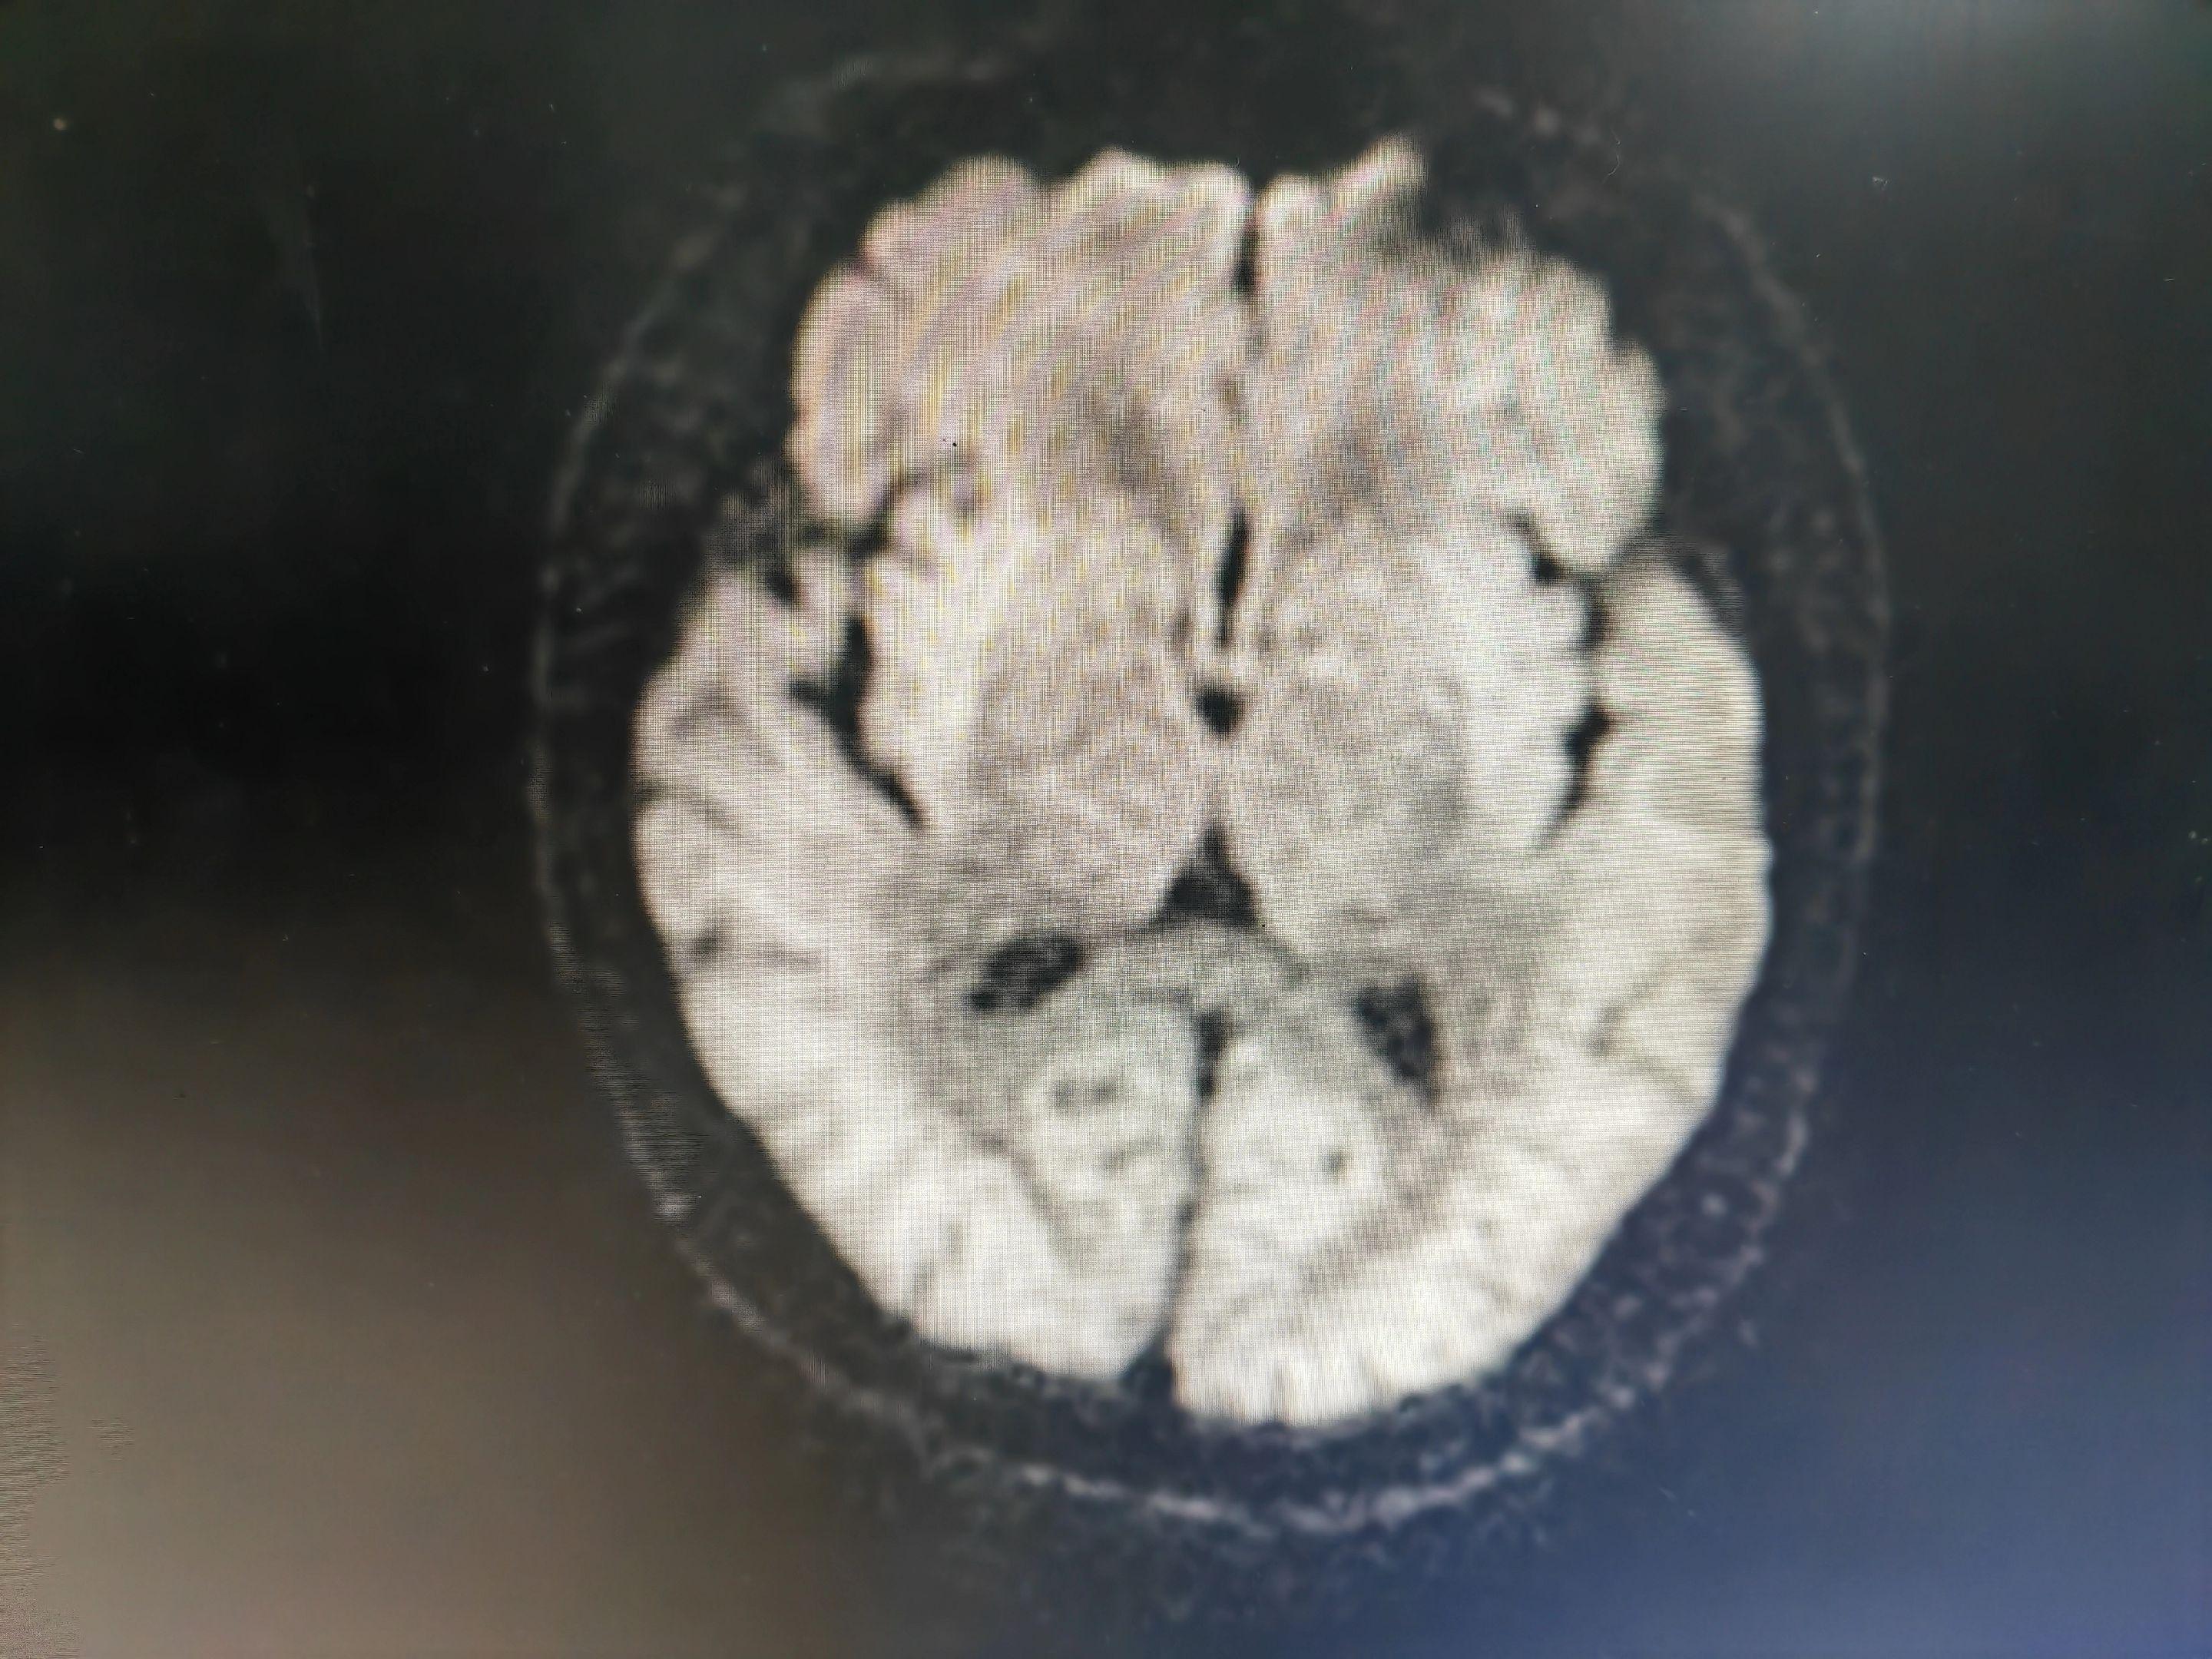

意识模糊伴言语不清的病人 中毒代谢性脑病几种最重要的影像学表现:白色即为受累区域,包括双侧对称性基底节和/或丘脑受累(图A),对称性齿状核受累(图B),皮层灰质受累(图C),对称性脑室周围白质受累(图D),皮质脊髓束受累(图E),胼胝体受累(图F),不对称性白质受累(脱髓鞘疾病;图G),枕顶枕部血管源水肿(图H),脑桥中央受累(I)。